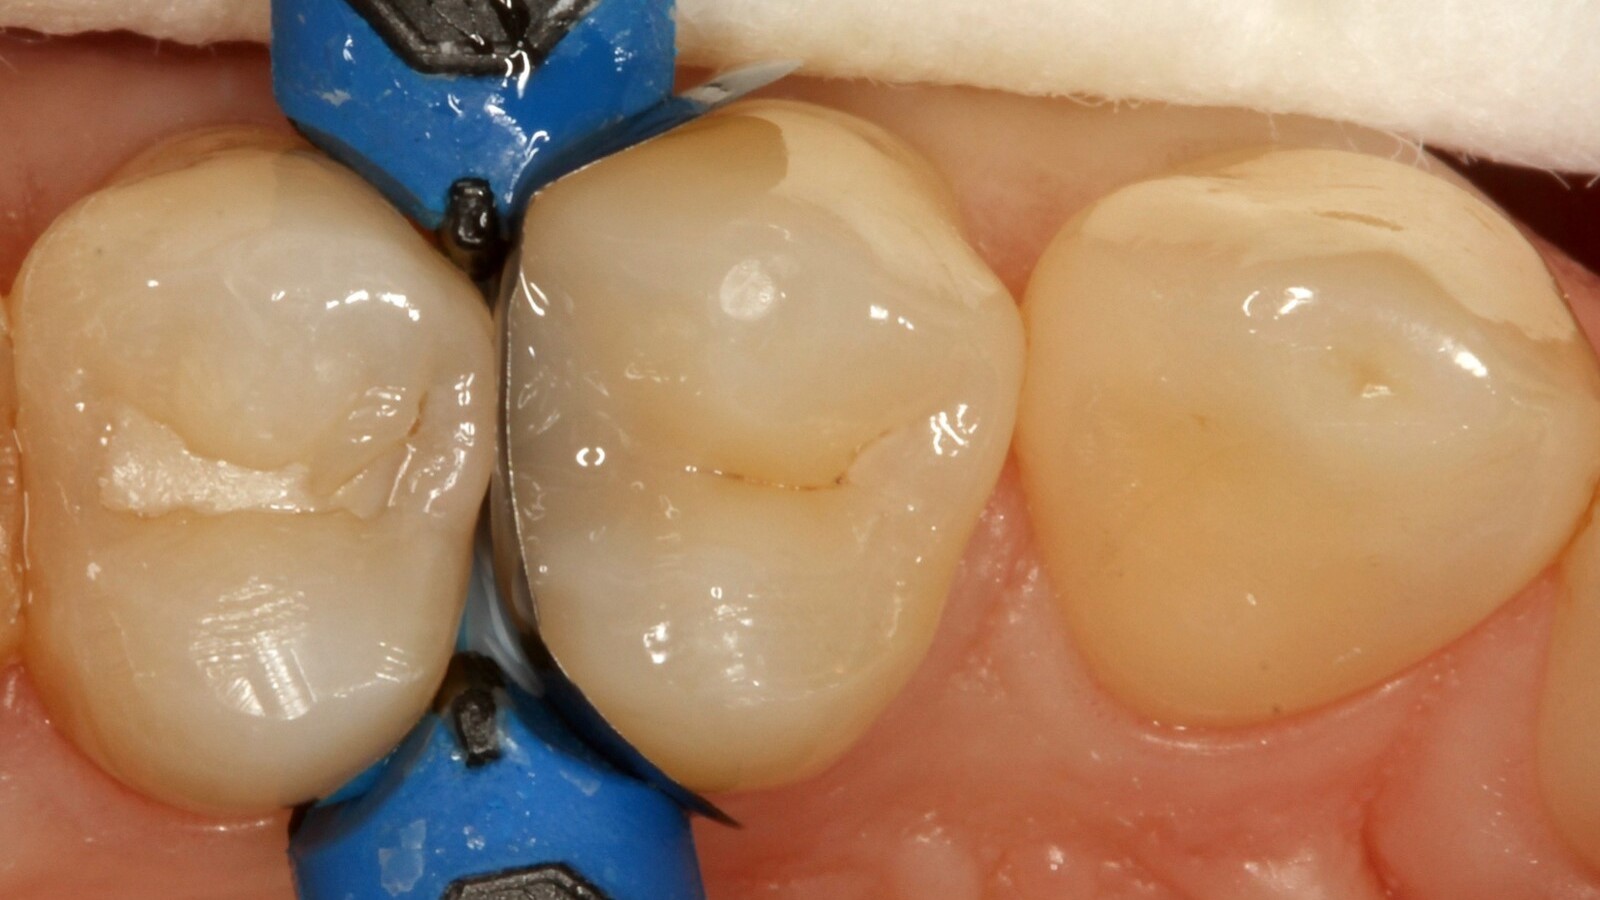

Le professeur Ernst a d'abord identifié les caries non visibles et a ouvert la lésion carieuse pour montrer le problème au patient (Fig. 1-2). Il a ensuite excavé la carie, préparé la cavité et placé une matrice sectionnelle (Fig. 3) avant de sceller la cavité avec de l'adhésif (Fig. 4). En une seule étape, il a rempli la cavité avec Venus Bulk Flow ONE (Fig. 5). Une fois la restauration terminée, le Pr Ernst l'a polie (Fig. 6) et a pris une radiographie de contrôle, qui montre également l'excellente radiopacité de Venus Bulk Flow ONE (Fig. 7).